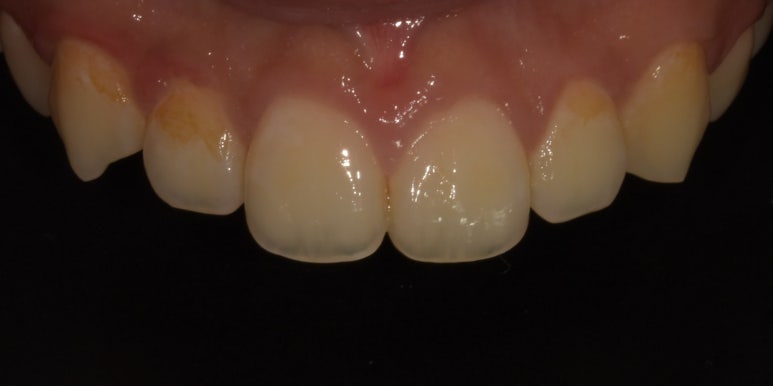

법랑질성형 시술사례

사진을 보시면 법랑질성형 후 날카로웠던 부분 및 앞니 2개의 끝부분이 다듬어져

훨씬 깔끔하고 정돈된 느낌이 드는 것을 확인하실 수 있습니다.